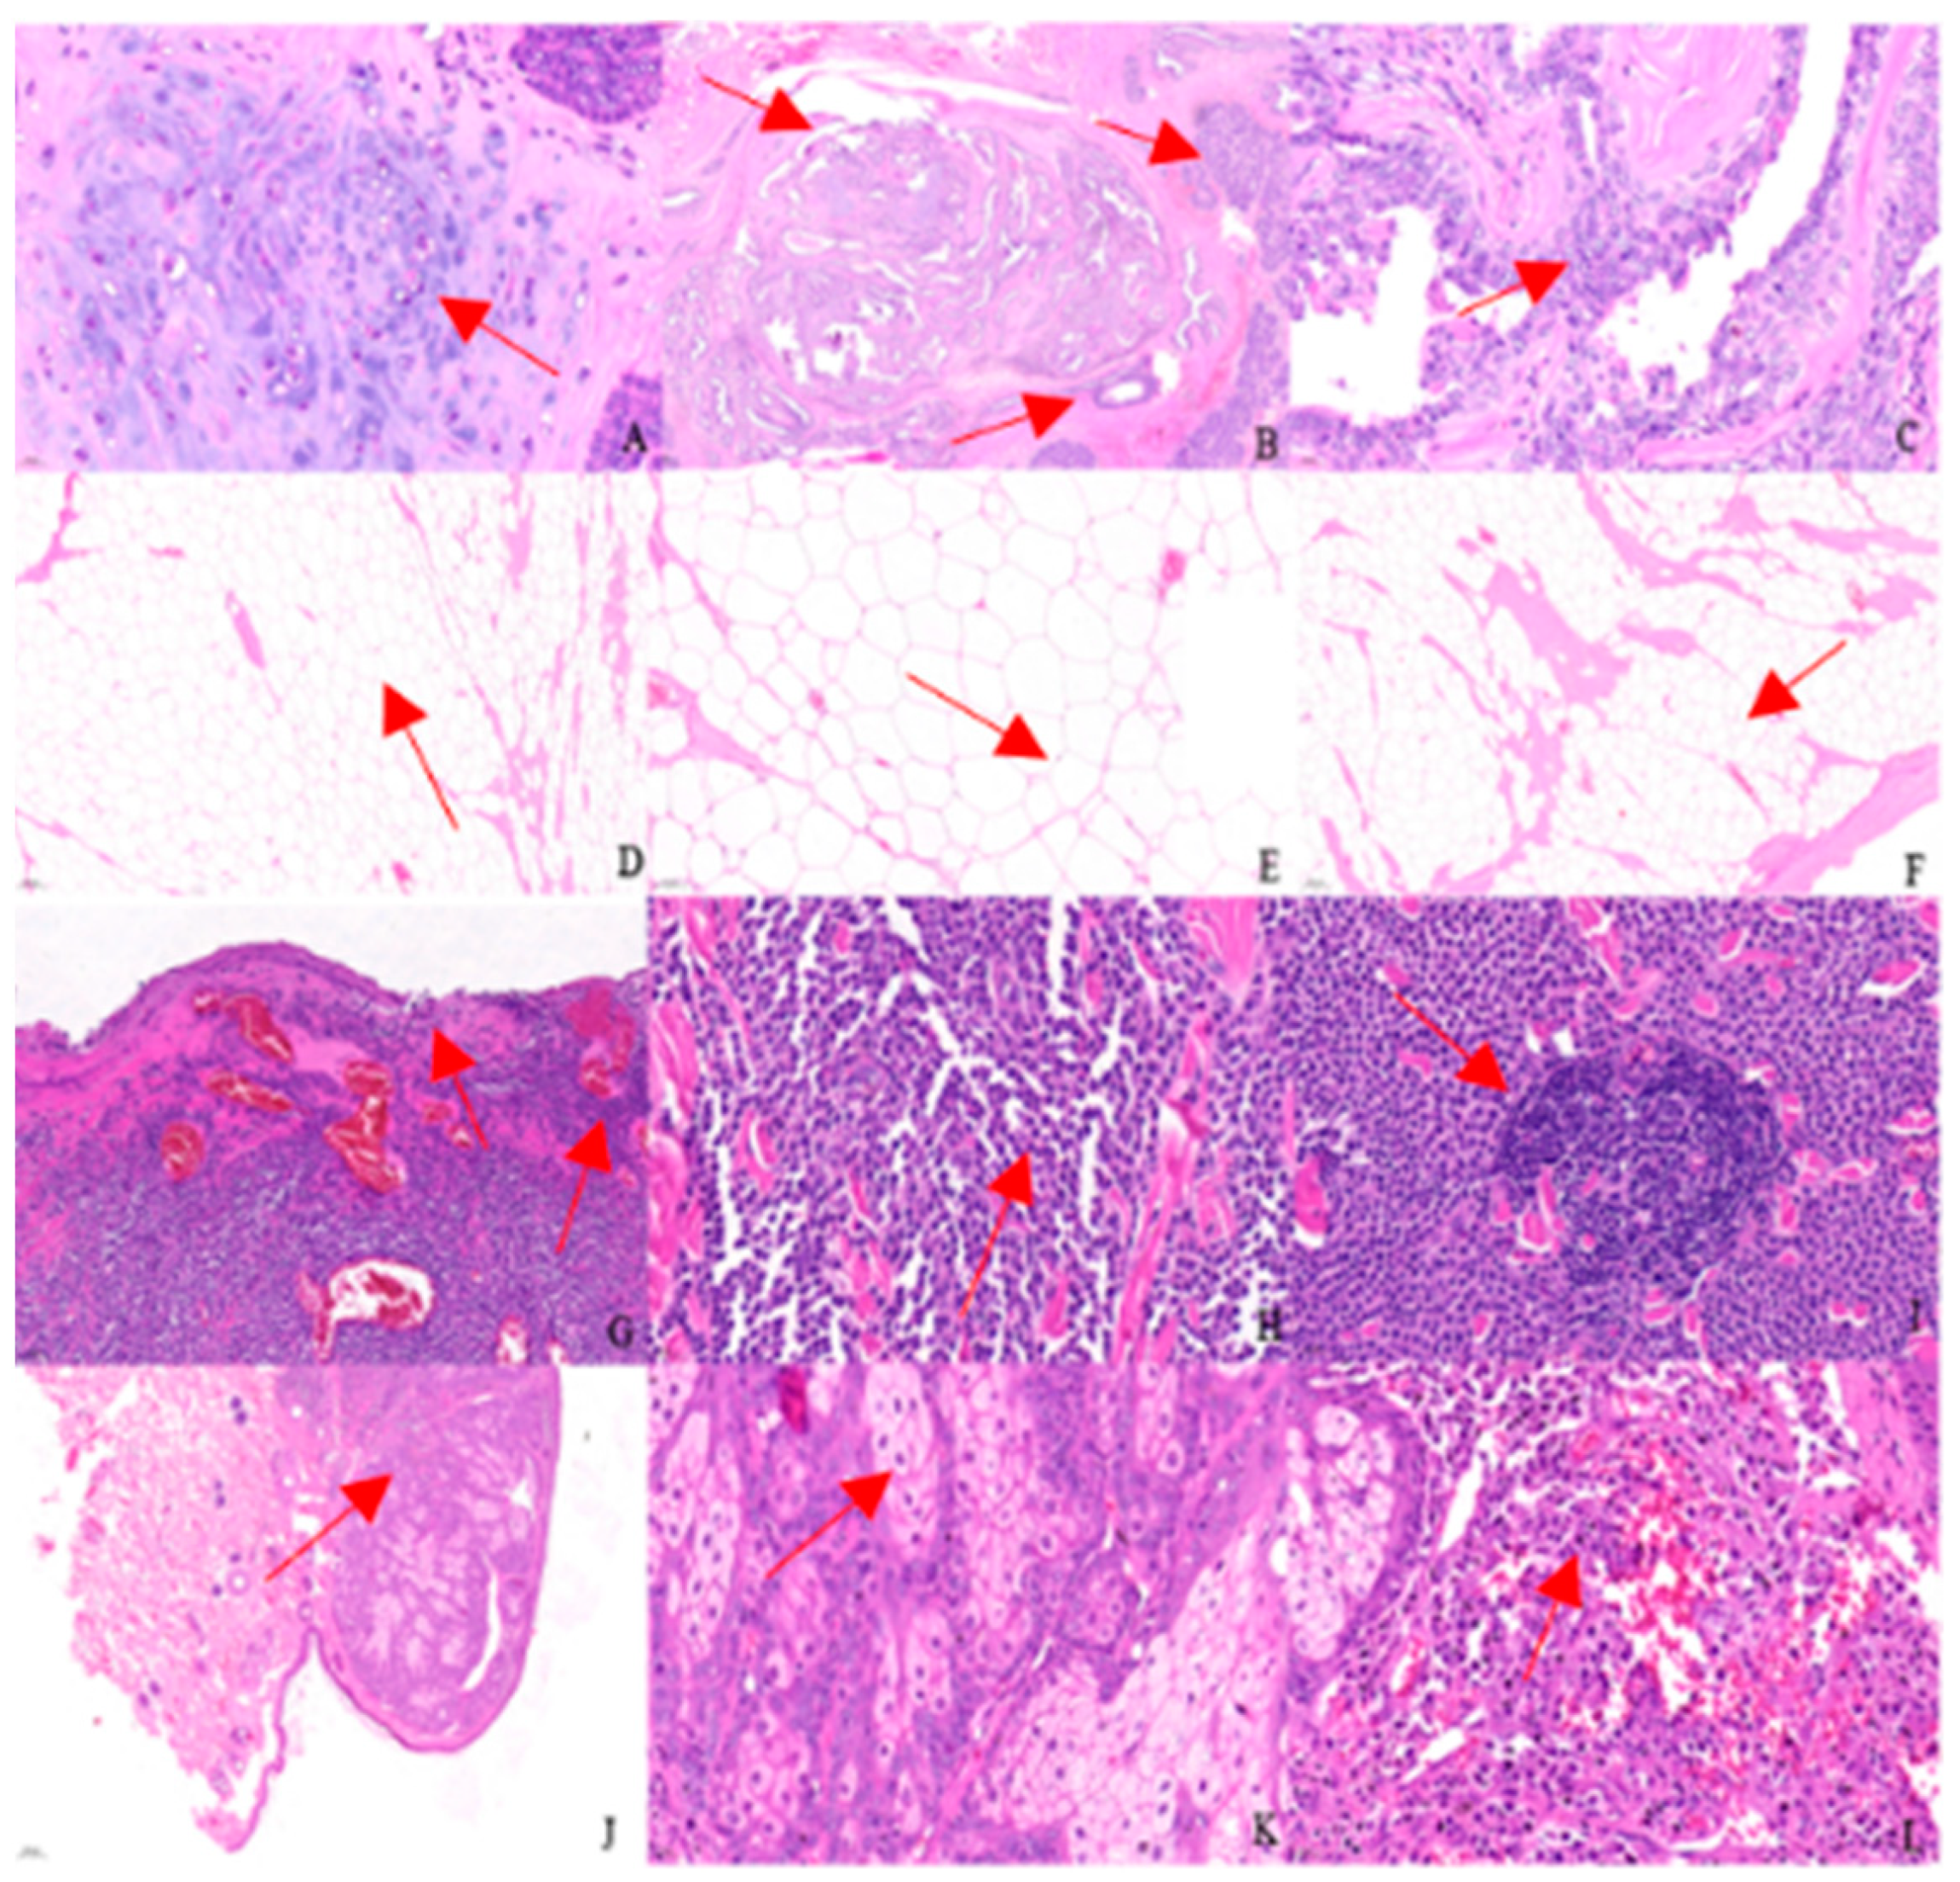

2.6. Pathology Examination

3.5. Pathology Examination